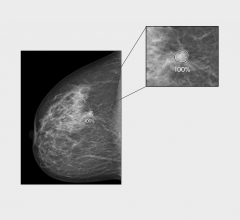

Mammography is a breast imaging technique that uses X-rays to diagnose and locate tumors of the breasts.